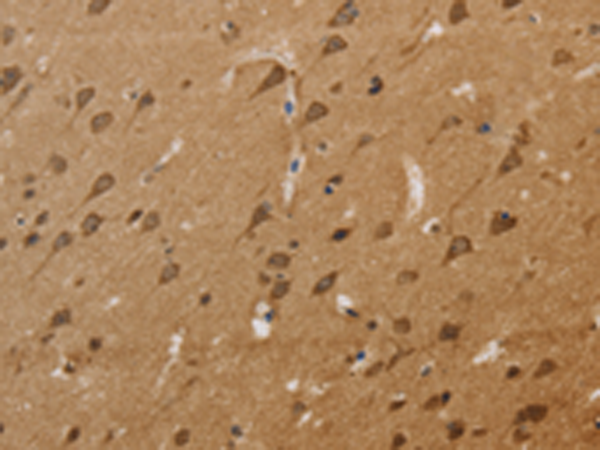

分类: 科研抗体货号: P05124别名: OT-R应用: IHC反应种属: Human, Mouse, Rat

分类: 科研抗体货号: P05048别名: GL004; C2orf33应用: IHC反应种属: Human, Mouse, Rat